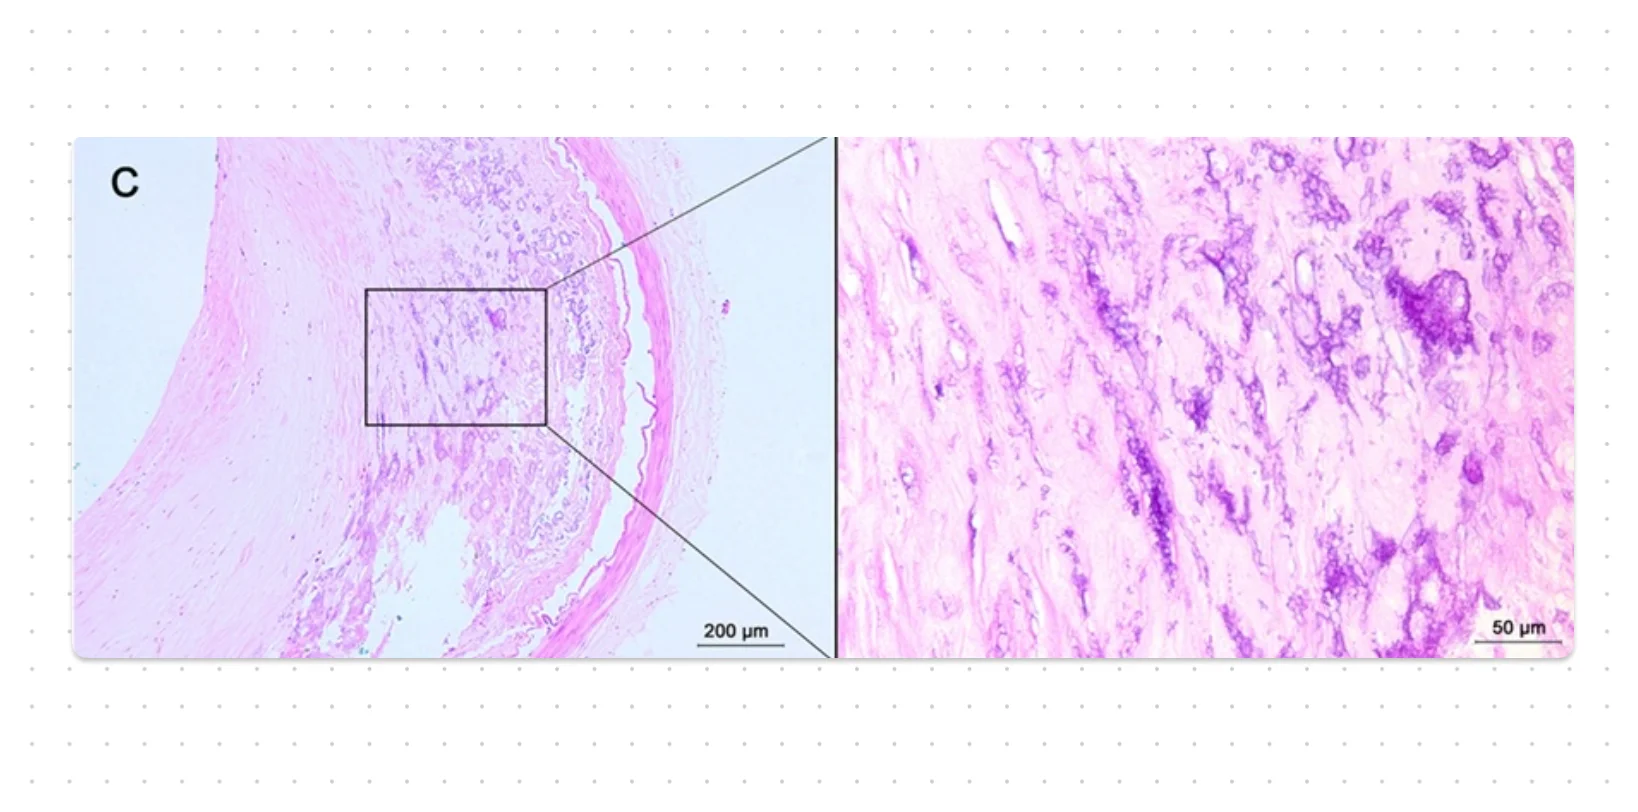

- It is almost universally found in the arterial lesions of advanced atherosclerosis.

- The image used in the cover photo is licensed under the Creative Commons Attribution 4.0 International license. Source: "Histological Characteristics of Intracranial Atherosclerosis in a Chinese Population: A Postmortem Study". Frontiers in Neurology 8. DOI:10.3389/fneur.2017.00488. ISSN 1664-2295.